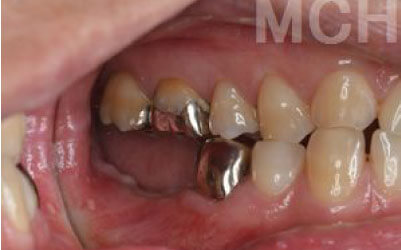

ブリッジとインプラントでは、周りの歯の寿命に大きな違いがあります。ブリッジは支えとなる歯を健康でもかなり削らなければならず、さらに噛む力が約1.5倍かかるため、その歯の寿命が短くなってしまいます。実際のデータでは、ブリッジの支えとなった歯の68%が10年以内に抜歯に至っています。

ブリッジ治療の場合も、失った歯にかかっていた力を前後の歯が支えるため、結果として残っている歯には、通常の1.5〜2倍ほどの負荷がかかってしまいます。

ブリッジなどの治療では、前後の歯を大きく削らなければならず、場合によっては虫歯でなくても神経を抜くことがあります。神経を抜いて被せ物をすると、その歯は一気に寿命の終わりに近づいてしまうのです。

残っている歯にとって、ブリッジ治療は非常にもったいない方法です。

その理由は、ブリッジを作るために前後の歯を大きく削らなければならないからです。

場合によっては、神経を取る必要があることもあります。

これだけ歯にダメージを与えるため、その歯の寿命が大きく縮むことになります。

最も大きな違いは、前後の歯の寿命に影響を与えることです。

ブリッジでは、抜けた歯の前後の歯を大きな虫歯と同じくらいまで削らなければならず、

また、抜けた歯の代わりに前後の歯がその力を支えるため、常に1.5倍の負荷がかかります。

1)ブリッジ

2)歯を大きく削る+支えの歯に1.5倍の力がかかる

3)前後の歯の寿命が著しく減る

ブリッジの支えの歯は、データでは10年以内に68%が抜歯になります。